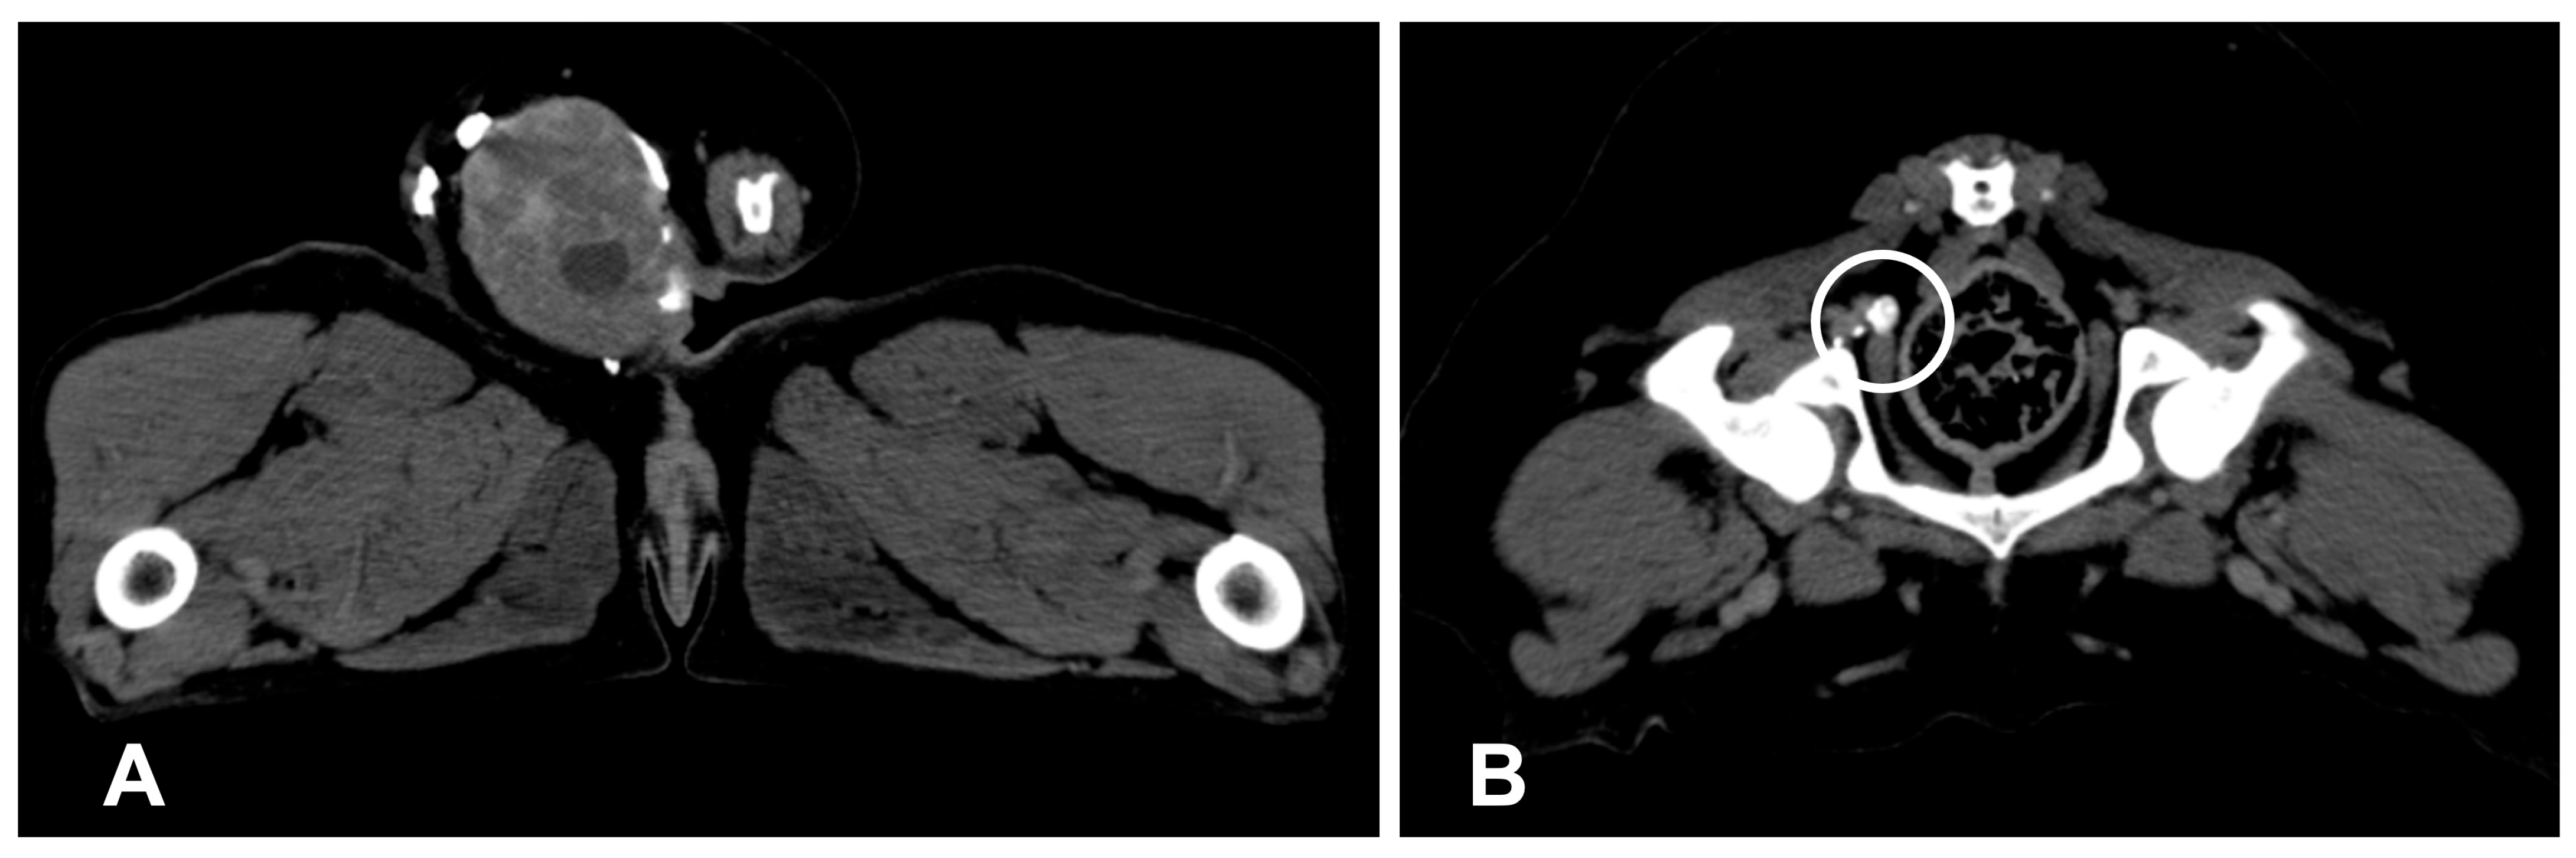

- Majeski, S.A.; Steffey, M.A.; Fuller, M.; Hunt, G.B.; Mayhew, P.D.; Pollard, R.E. Indirect Computed Tomographic Lymphography for Iliosacral Lymphatic Mapping in a Cohort of Dogs with Anal Sac Gland Adenocarcinoma: Technique Description. Vet. Radiol. Ultrasound Off. J. Am. Coll. Vet. Radiol. Int. Vet. Radiol. Assoc. 2017, 58, 295–303. [Google Scholar] [CrossRef]

- Rossi, F.; Korner, M.; Suarez, J.; Carozzi, G.; Meier, V.S.; Roos, M.; Rohrer Bley, C. Computed tomographic-lymphography as a complementary technique for lymph node staging in dogs with malignant tumors of various sites. Vet. Radiol. Ultrasound Off. J. Am. Coll. Vet. Radiol. Int. Vet. Radiol. Assoc. 2018, 59, 155–162. [Google Scholar] [CrossRef]